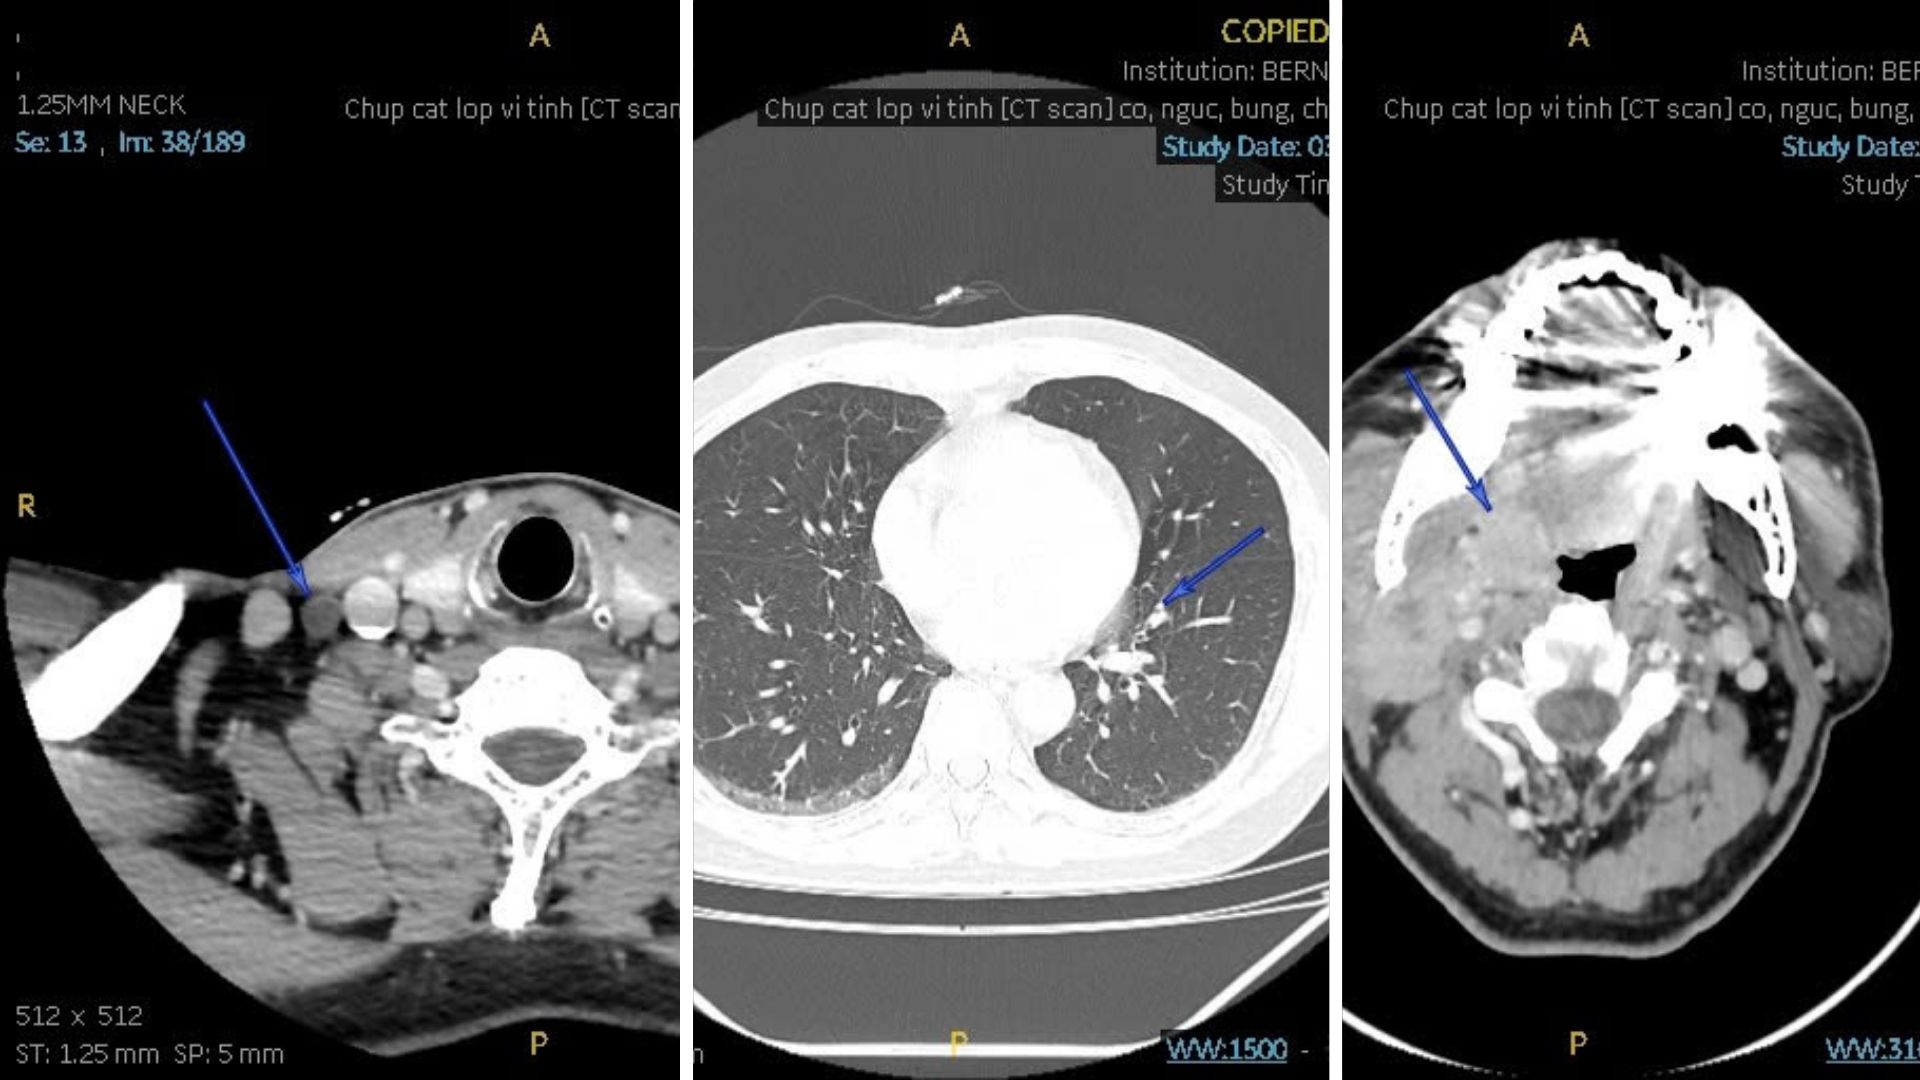

Trên cơ sở đó, bệnh nhân được chỉ định chụp CT Scan cổ - ngực - bụng - chậu nhằm đánh giá toàn diện khả năng di căn và xác định mức độ tiến triển của bệnh.

Kết quả CT Scan ghi nhận có khối choán chỗ khẩu hầu mức amygdale (phải), kích thước 1,9 x 2,1 cm, bờ không đều, bắt quang trung bình, nghi ngờ u ác và hạch lớn khoang cảnh phải (2 x 2,9 cm), bắt quang không đồng nhất, có hoại tử. Những đặc điểm này gợi ý tổn thương đã di căn hạch cổ.

Các cơ quan tim, phổi, gan-thận không ghi nhận bất thường ác tính, chỉ có một số tổn thương xương cũ và thoái hóa cột sống đi kèm.

Kết luận từ chuyên gia chẩn đoán hình ảnh Bernard là tổn thương choán chỗ amidan phải kèm hạch lớn vùng cổ phải, phù hợp phân loại T2N1Mx (giai đoạn III). Điều này cho thấy khối u đã lan đến hệ bạch huyết vùng cổ - tức đã có di căn hạch vùng.

Đánh giá từ chuyên gia Nhật Bản đồng ý rằng đây là ung thư amidan phải và di căn nhiều hạch cổ phải. Bệnh nhân được khuyến cáo thực hiện MRI vùng cổ để đánh giá rõ ràng hơn mức độ xâm lấn mô mềm và chụp FDG-PET để đánh giá phạm vi di căn.